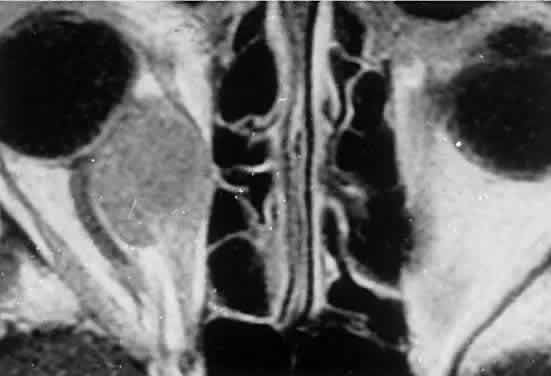

Fig. 2. MRI shows an intraconal tumor of lower intensity than the medial rectus

muscle. The proximal muscle is splayed rather than compressed, suggesting

that the lesion originated within the medial rectus. The diagnosis

was alveolar rhabdomyosarcoma. Fig. 2. MRI shows an intraconal tumor of lower intensity than the medial rectus

muscle. The proximal muscle is splayed rather than compressed, suggesting

that the lesion originated within the medial rectus. The diagnosis

was alveolar rhabdomyosarcoma.